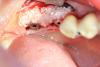

ВИТА Опубликовано 17 августа, 2012 Автор Поделиться Опубликовано 17 августа, 2012 ну вот как то так я делаю...........с помощью спец набора для расщепления........гребень был мм 3, поставила импланты 3,75 в облати 36 и 4,5 в области 37 АВ Ссылка на комментарий

kmatv Опубликовано 17 августа, 2012 Поделиться Опубликовано 17 августа, 2012 Все вроде и ни чего для начального опыта сплита. Только расщепления-то не было. Судя по фото, вестибулярная стенка даже не сдвинулась, и вы выпилили весь кортикальный слой. Т.е.можно было и не делать распилы. Надо делать послабляющий распил внизу. Ссылка на комментарий

ВИТА Опубликовано 17 августа, 2012 Автор Поделиться Опубликовано 17 августа, 2012 на самом деле гребень был очень узкий, но не такой конечно, как тут...... Ссылка на комментарий

kmatv Опубликовано 17 августа, 2012 Поделиться Опубликовано 17 августа, 2012 Вита, вы не обижайтесь, но тогда смысл этих пропилов? Если кортикалка даже не сдвинулась?! Сплит направлен на раздвижение и сохраниение кортикальной пластинки. Если чувствуете излишнюю подвижность, и высокую вероятность отлома, подфиксируйте минивинтами, и продолжайте закручивать импланты.. Ссылка на комментарий

Mane Опубликовано 21 августа, 2012 Поделиться Опубликовано 21 августа, 2012 Тоже поддержку что расщепления здесь и не было. Ситуация еще хуже чем в теме "расщепление по карлосу" которое представил биер. Не хватает горизонтального пропила внизу что как раз и дало бы почву для сплита. Опять же вы просто вписали эти имплантаты в то что было и сверху просыпались. Блоков не нужно бояться. Если их делать много и часто то результат вас будет так радовать, что расщепление вам делать уже не захочется. Без обид. 1 Ссылка на комментарий